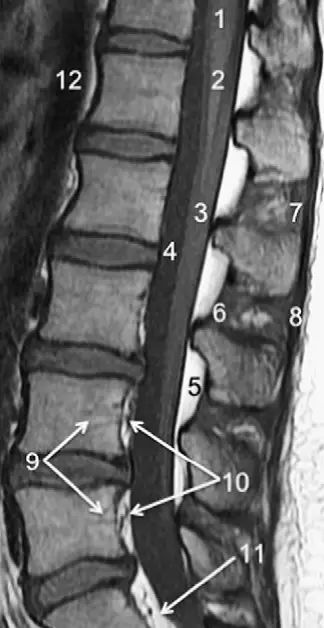

脊柱的MRI解剖

3、MRI:可显示骨折所致血肿及脊髓损伤所表现出的异常高信号。(平扫)

7、棘间韧带:是连于棘突(D9)之间的短韧带。

8、棘上韧带:起于第7颈椎的棘突,延伸至骶骨,参与构成椎骨与骶骨的连结。

2、前纵韧带:起自枕骨或寰椎前结节,沿椎体的前面向下延伸至骶骨,该韧带下端增宽,与椎体紧密相连,但与椎间盘连结较松。

3、后纵韧带:沿椎体的后面走行,分为浅、深两层。